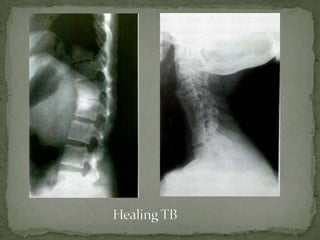

Conventional Radiographs –

 healing is appreciated late on routine radiographs

 lags behind by about 3 months

 Bony changes may even progress till 14 months after starting

treatment and should not necessarily be considered an

adverse feature

 Soft tissue paravertebral masses may also progress while on

treatment reaching a maximum size within 1.5

months, although they may take up to 15 months to resolve

Radiographic signs of healing –

 static lesion

 regression of a lesion

 well-defined outlines of the lesion

 evidence of sclerosis

 fusion of adjacent vertebral bodies forming a large block of

osseous mass

 Fusion of contiguous vertebrae has been regarded as the

surest sign of healing of spinal tuberculosis